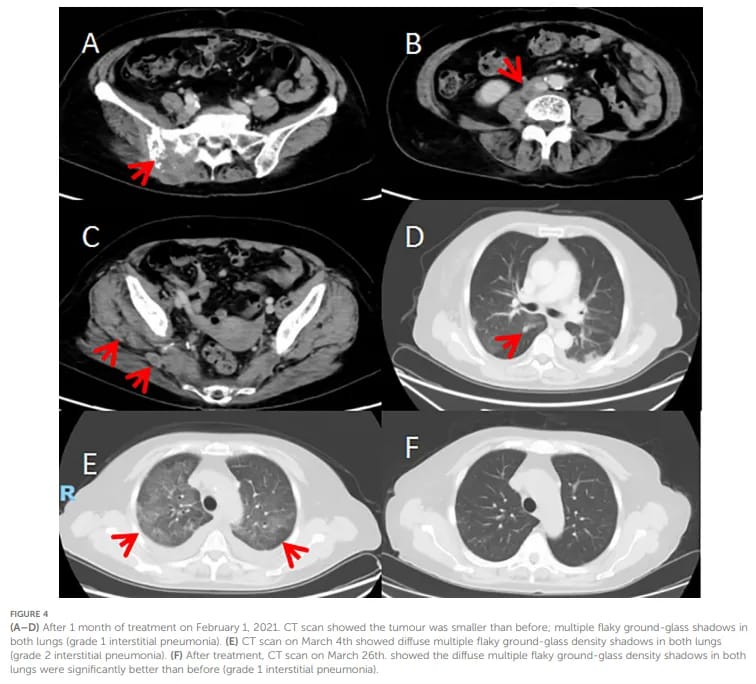

令人鼓舞的是,治疗取得了初步成效。患者的疼痛症状明显改善,一个月后的CT扫描显示肿瘤缩小了26%,评估为疾病稳定(SD)。然而,治疗过程并非一帆风顺。患者随后出现了2级间质性肺炎,这是一种mTOR抑制剂较为严重的副作用,不得不暂停用药。经过积极处理,肺炎好转后,患者继续依维莫司治疗,并一度联合了抗血管生成药物安罗替尼,病情保持了长时间的稳定。整个一线治疗阶段,患者获得了长达17个月的无进展生存期。